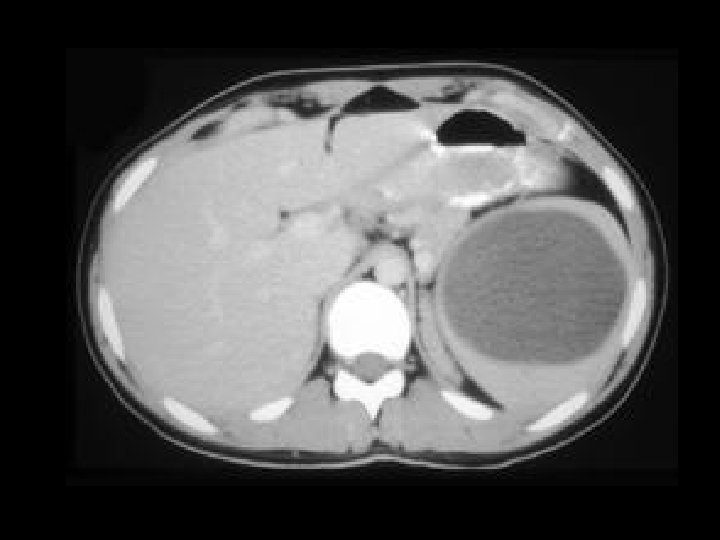

Pancreatic pseudocysts • Findings: – Multiple large pancreatic cystic lesions • ddx: – Von-Hippel Lindau – Cystic pancreatic neoplasm